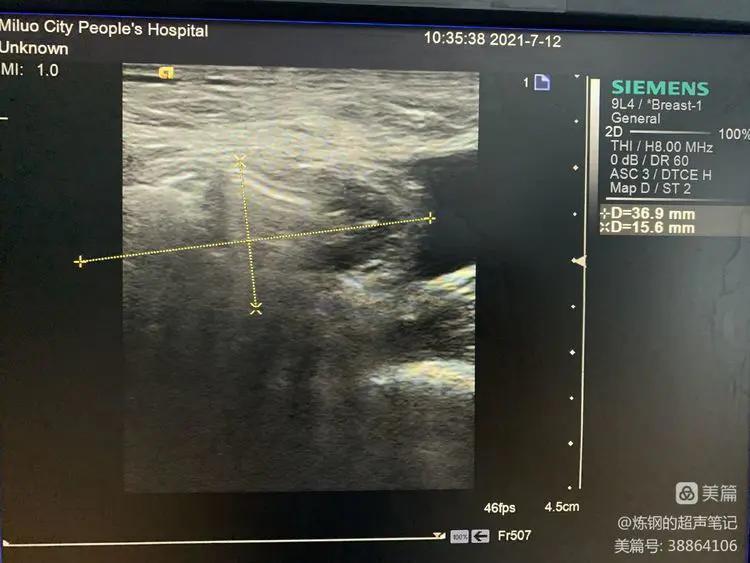

男,67岁,左侧腹股沟肿块一年多,拟左侧腹股沟斜疝手术术前常规检查!

超声显示:左侧腹股沟斜疝,右侧腹股沟斜疝+右侧股疝!

下面图片及视频为右侧腹股沟斜疝及股疝:

乏氏动作时股疝大小